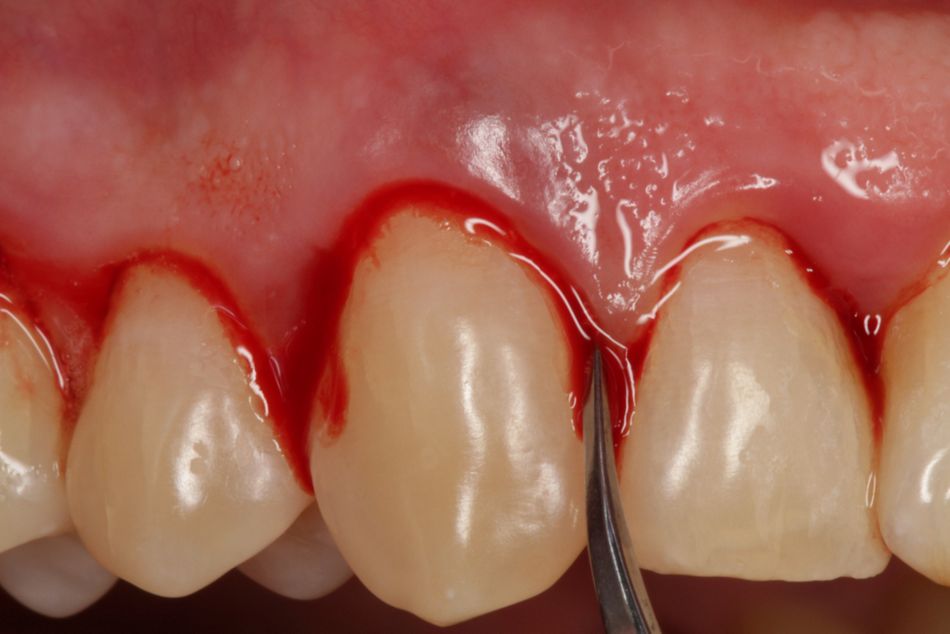

Ultimately, it is just another “surgical” approach. I don’t use a scalpel, but rather a periosteal elevator or a papilla elevator and I widen the gingiva. Once I have good access, I work with curved Slimline ultrasound attachments. They are not sharp and the tip is cooled, i.e. I can also work subgingivally and do not risk damage to tissue posed by thermal trauma. I have coined the term “tension flap” to describe the procedure.

Bröseler: “I find these fine cannulae very practical in reaching the bony base of the defect.”

Fig. 9: Straumann® Emdogain® FL for minimally invasive flapless surgery. The fine cannula makes it easier to apply the gel.